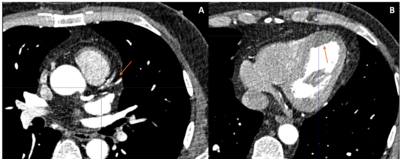

A 60-year-old male with no prior medical history presented with lightheadedness and stable exertional chest pain. Vital signs and physical examination were unremarkable. Electrocardiogram showed normal sinus rhythm with an old inferior and anteroseptal infarction. Echocardiography revealed normal EF with no clear wall motion abnormalities. A myocardial perfusion stress test showed moderate fixed reduced radiotracer uptake with mild reversibility at the LAD territory (Figure 1). Coronary computed tomography angiography revealed a calcified and non-calcified plaque in the proximal to mid LAD with apical LVT (Figure 2[A-B]). Left heart catheterization showed a total mid LAD occlusion with collateral circulation from the acute marginal branch of the right coronary artery to distal LAD (Figure 3[A-B]). Further work-up revealed a JAK2 V617F mutation. The patient was treated with apixaban, atorvastatin, and metoprolol.